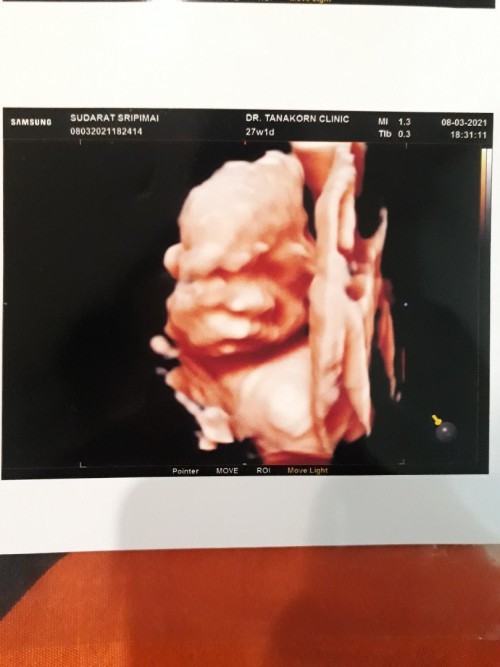

ภาพซาวด์4มิติ

ขอดูภาพซาวด์4มิติ ของแม่ๆท่านอื่นหน่อยคะ บ้านนี้ซาวด์ปัยน้องยิ้มเล่นไปด้วย ให้ทายว่าน้องเปนผญ.หรือผช.😊